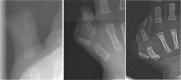

Background: Thumb epiphyses cannot be visualized on radiographs in infants with radial polydactyly, making it difficult to classify by Wassel type. The purpose of this study was to identify radiographic features that distinguish a separate epiphysis from a shared epiphysis. This may assist in operative planning and establishing prognosis.

Methods: The charts of 34 radial polydactyly patients treated with surgical reconstruction from 2008 through 2012 were retrospectively reviewed. Measurements of the most proximal bones involved in the duplication, including length, width at shaft, width at base, distance between radial and ulnar thumb, and angle between radial and ulnar thumb, were taken from PA radiographs of the thumb by four blinded individuals. The interclass correlation coefficient was calculated to determine inter-observer reliability. Operative notes were reviewed to distinguish between shared and separate epiphyses. Several indices were created from these measurements.

Results: Radiographic measurements showed high inter-observer reliability. There were statistically significant differences between patients with separate and shared epiphyses for indices for the width shaft index, interspace distance, the angle × interspace distance, and the angle × interspace index.

Conclusion: Radiographic differences exist between children with separate and shared epiphyses. In patients with shared epiphyses, the radial thumb tends to be smaller, closer to the ulnar thumb, and less divergent. Threshold values were identified for predicting the status of the epiphysis based on the angle × interspace distance and the angle × interspace index. These values may be used to help determine in advance of surgery if a shared epiphysis exists.